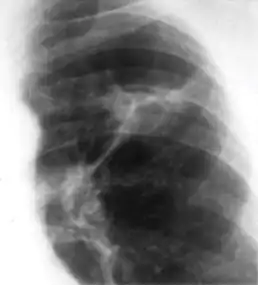

Chest x-ray of Ghon's complex of active tuberculosis

Ghon's complex is a lesion seen in the lung that is caused by tuberculosis.[1][2] The lesions consist of a Ghon focus along with pulmonary lymphadenopathy within a nearby pulmonary lymph node. A Ghon's complex retains viable bacteria, making them sources of long-term infection, which may reactivate and trigger secondary tuberculosis later in life.[3]

In countries where cow milk infected with Mycobacterium bovis has been eliminated (due to culling of infected cows and pasteurization), primary tuberculosis is usually caused by Mycobacterium tuberculosis and almost always begins in the lungs. Typically, the inhaled bacilli implant in the distal airspaces of the lower part of the upper lobe or the upper part of the lower lobe, usually close to the pleura. As sensitization develops, a 1 to 1.5 cm area of gray-white inflammation with consolidation emerges, known as the Ghon focus. In most cases, the center of this focus undergoes caseous necrosis. Tubercle bacilli, either free or within phagocytes, drain to the regional nodes, which also often caseate. This combination of parenchymal lung lesion and nodal involvement is referred to as the Ghon complex. During the first few weeks, there is also lymphatic and hematogenous dissemination to other parts of the body.